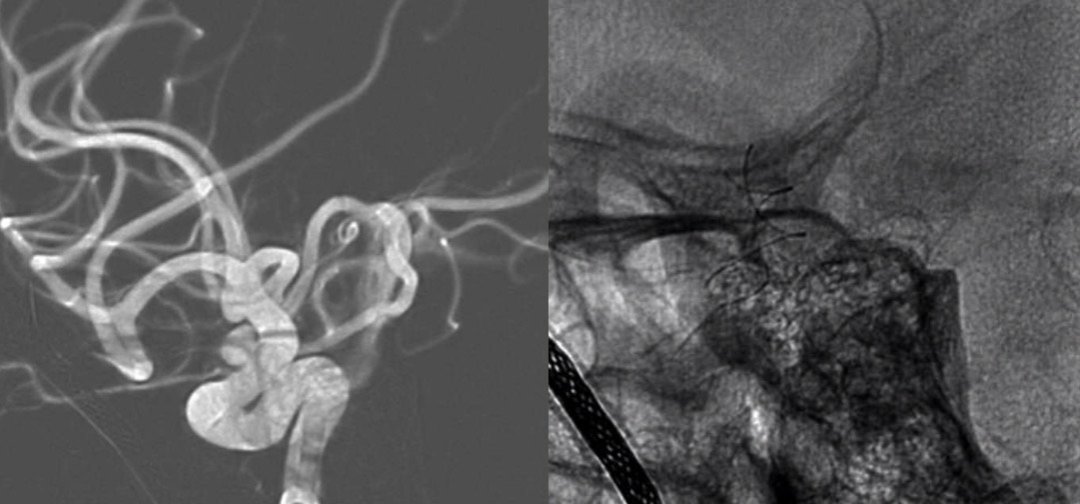

图3 造影可见双侧颈内动脉动脉瘤

图4 经T-track微导管释放Tubridge 4.5x20 mm支架一枚

全麻满意后,常规消毒铺巾,采用改良 Seldinger技术穿刺右侧股动脉成功,置入6F动脉鞘。150 cm超滑泥鳅导丝带领5F单弯造影管分别行左侧椎动脉、双侧颈总动脉正侧位造影及双侧颈内动脉三维旋转造影,结果显示:左侧颈内动脉C6段动脉瘤;右侧颈内动脉C6段多发动脉瘤。向患者家属交代病情,考虑左侧颈内动脉C6段动脉瘤瘤体较大,且形态不规则,遂行左侧颈内动脉C6段动脉瘤密网支架置入术。150 cm超滑泥鳅导丝携 6F ENVOY DA导引导管达左侧颈内动脉C2段,Synchro-14微导丝携T-track支架微导管进入左侧大脑中动脉M1段,调整管头位置满意,管腔接高压肝素生理盐水持续滴注。经 T-track微导管送入Tubridge 4.5 mmx20 mm支架一枚,调整位置满意后精准释放,完全覆盖动脉瘤,即刻造影显示支架打开良好,贴壁良好,动脉瘤瘤腔内造影剂滞留明显,载瘤动脉通畅。遂结束手术。